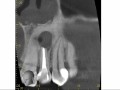

Odbudowa zębów po leczeniu kanałowym (...)

Katarzyna Olczak